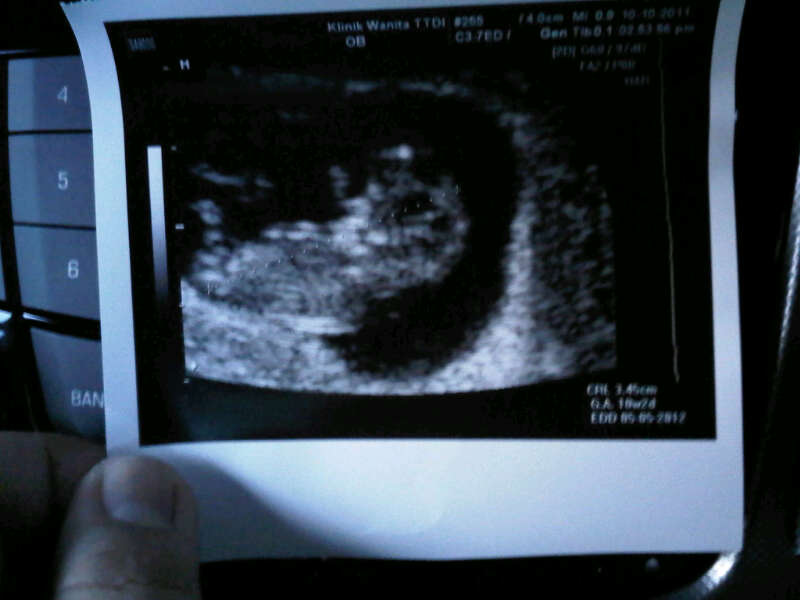

Assalam semua! Ni gambar baby masa let checkup. 10weeks++..Alhamdulillah, loya dah makin kurang. Tapi migrain menjadi2 plak. Ntah nape. Pastu takde selera makan. Tak tau nak makan apa. Tapi kalo jumpa ikan bilis,macam laju plak makan.Hm...apa2 pun,harap baby sihat membesar. Berat masih tak bertambah. Perut pon tak nampak sangat lagi.hehe. arini start selsema plak.dok makan panadol jer. Tak berani nak makan ubat lain. Baru balik keje,nak rest jap.daaaaa